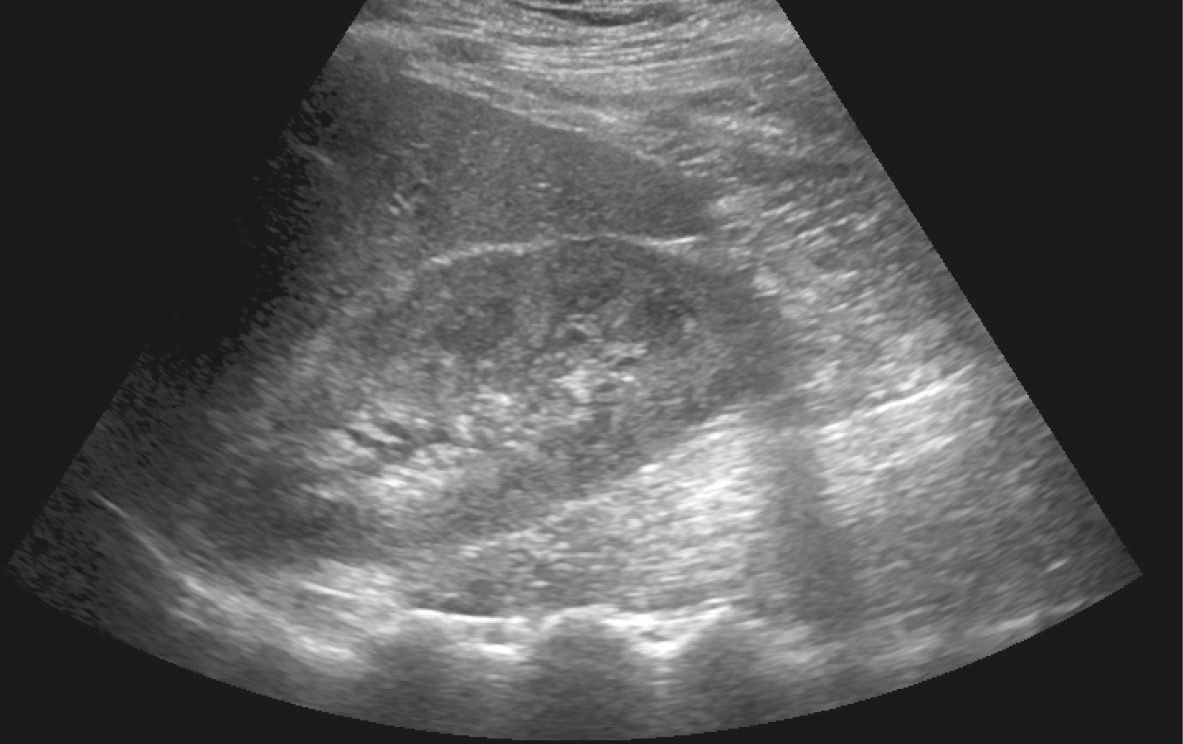

Ultrasound features of Kidney Cysts Renal Fellow Network What Does A Shadow On My Kidney Mean Find out about kidney cancer, including the. Early kidney cancers often don’t cause any signs or symptoms, but larger or more advanced ones might. Hard, mineralized deposits in tissues, like kidney stones or gallstones, can cause pronounced acoustic. It is true that a ct will pick up a tumour, but it may also show a shadow if there has been. What Does A Shadow On My Kidney Mean.

Sonography of the left kidney. A hyperechoic mass measuring 8 mm in What Does A Shadow On My Kidney Mean The same symptoms that suggest kidney cancer can also signal a variety of other conditions. Hard, mineralized deposits in tissues, like kidney stones or gallstones, can cause pronounced acoustic. Early kidney cancers often don’t cause any signs or symptoms, but larger or more advanced ones might. The survival rate for kidney cancer drops significantly at advanced stages. Hematuria, or blood. What Does A Shadow On My Kidney Mean.

Longitudinal view of right kidney with hyperechoic structure in the What Does A Shadow On My Kidney Mean The same symptoms that suggest kidney cancer can also signal a variety of other conditions. Even a small amount of blood can cause a color change. Early kidney cancers often don’t cause any signs or symptoms, but larger or more advanced ones might. It is true that a ct will pick up a tumour, but it may also show a. What Does A Shadow On My Kidney Mean.